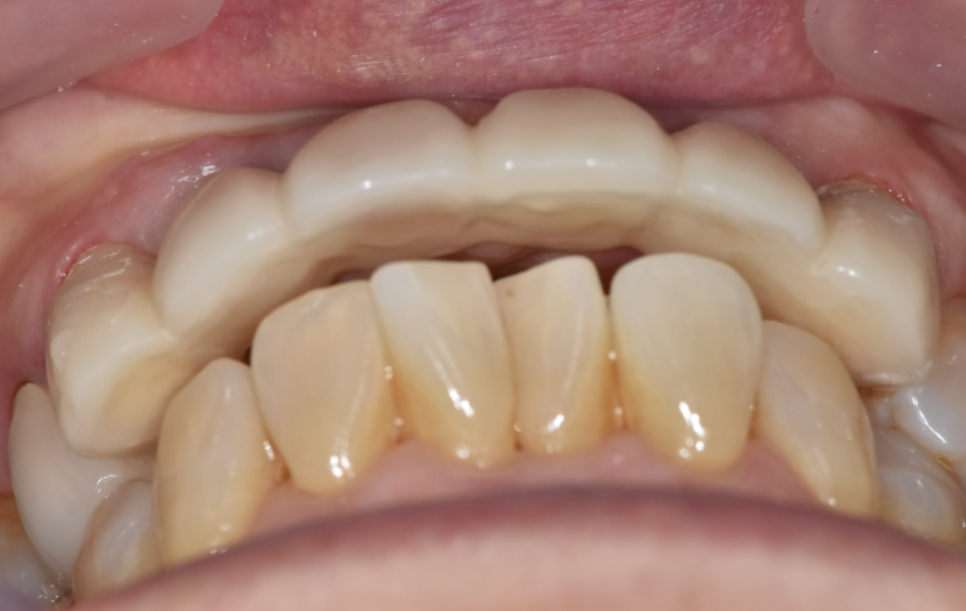

환자분 아래 앞니도 원래 약간 앞으로 나와 있는 편이셨어요.

위 치아가 아래 치아를 덮는 구조인데,

삭제량이 적으면 위 치아가 더 나와 보일 수 있습니다.

하지만 저희 병원에는 강력한 무기가 하나 있죠.

바로 원내 기공소!

발치 후 잇몸이 아무는 과정이 필요해서

그동안 임시치아를 쓰시는데요.

240708 임시치아

임시치아, 옆 위아래 모두 확인하여 조정

이 임시치아로 환자분과 크기나 모양에 대한 의견을 나눕니다.

기공소가 병원 안에 있으니까 환자분의 의견을 바로바로 반영 가능.